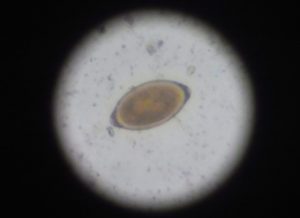

便検査を実施したところ、写真にあるように、「レモンの形」をした鞭虫に特徴的な形の卵が検出されました。